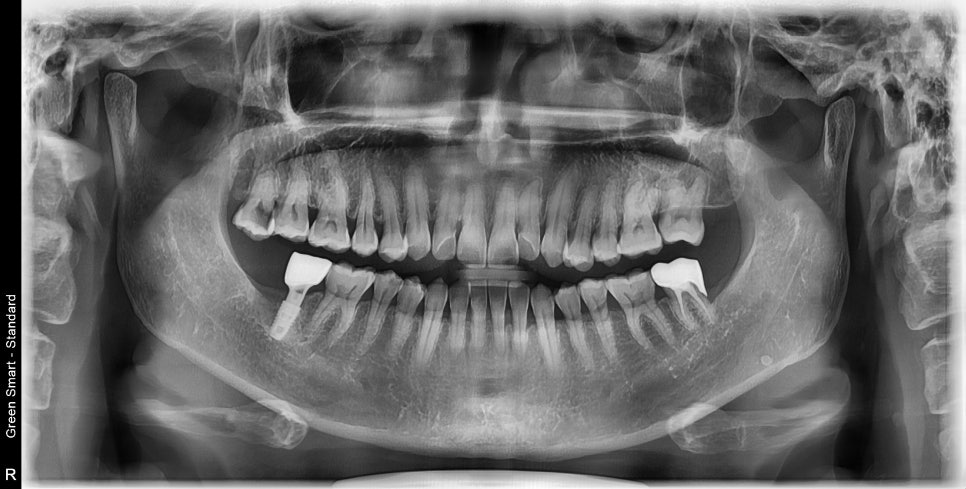

결국

해냈습니다.

21.5 ~ 24.4 이니까 3년이네요 ㅠ

그래도 환자분은 임플란트 안하고 해결했다는 점에 만족했습니다

사랑니이기 때문에 형태도 약간은 이상했지만 아래쪽과 교합도 문제없게 만들어드렸습니다.

유지장치 제작까지 해드리고 이제는 오랫동안 건강하게 사용하시길 바랍니다